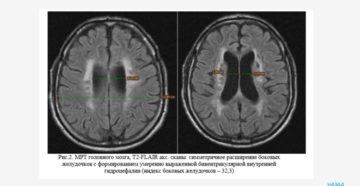

Что такое дилатация желудочков головного мозга Термин дилатация подразумевает расширение органа. Касается он не только…